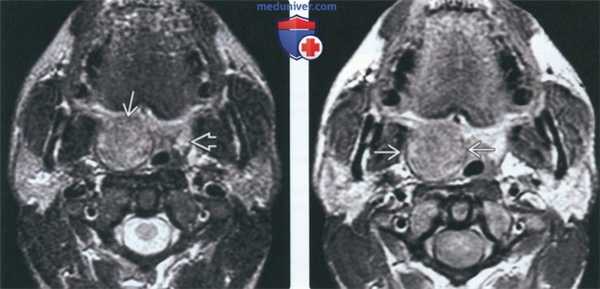

(Слева) На аксиальной МРТ (Т2 ВИ FS) определяется хорошо отграниченная НХЛ миндалины справа. Небольшой размер левой миндалины является нормой для взрослых людей, т. к. лимфоидная ткань подвергается возрастной инволюции. Плоскоклеточный рак миндалины и доброкачественная смешанная опухоль могут выглядеть идентично, диагноз НХЛ подтверждается только при помощи биопсии.

(Справа) На аксиальной МРТ (Т1 ВИ С+) у этого же пациента определяется однородное контрастирование НХЛ миндалины. При инфекционном поражении миндалин наблюдается «исчерченная» картина контрастного усиления, абсцесс миндалины характеризуется центральным некрозом.

(Слева) На аксиальной МРТ (Т2 ВИ FS) определяется мультифокальная НХЛ обеих небных миндалин. Четкие края позволяют предположить, что опухоль ограничена капсулой миндалин.

(Справа) На аксиальной МРТ (Т1 ВИ FS) у этого же пациента визуализируется дополнительный участок поражения лимфоидной ткани НХЛ в основании языка слева, а также крупный некротический лимфоузел IB уровня. Присутствуют множественные мелкие шейные лимфоузлы, однако лишь оценка метаболической активности с помощью, например, ПЭТ/КТ, позволяет выявить их поражение НХЛ.

(Слева) МРТ Т2ВИ FS МРТ, аксиальная проекция, на которой визуализируется неходжкинская лимфома правой небной миндалины, контуры образования четкие. Поскольку с возрастом объем лимфоидной ткани снижается, небольшой размер левой небной миндалины является нормой. Плоскоклеточный рак или доброкачественная смешанная опухоль могут выглядеть идентично, и только биопсия позволит установить диагноз лимфомы.

(Справа) МРТ Т1ВИ с КУ, аксиальная проекция, тот же пациент. Лимфома однородно накапливает контрастное вещество. При воспалении миндалины контраст бы накапливался отдельными полосами, в случае интра-тонзиллярного абсцесса в центре образования обнаруживается очаг некроза.

(Слева) MPT Т2ВИ FS в аксиальной проекции. В обеих небных миндалинах определяются мультифокальные лимфомы. Четкие края опухолей говорят о том, что они находятся в пределах капсул миндалин.

(Справа) MPT Т1ВИ FS с КУ, аксиальная проекция, этот же пациент. Определяется участок лимфомы в области лимфоидной ткани корня языка слева и крупный некротизированный лимфоузел IB уровня. На шее также визуализируются несколько мелких лимфоузлов, но установить, поражены ли они лимфомой, можно только при помощи метаболических исследований, например, ПЭТ/КТ.